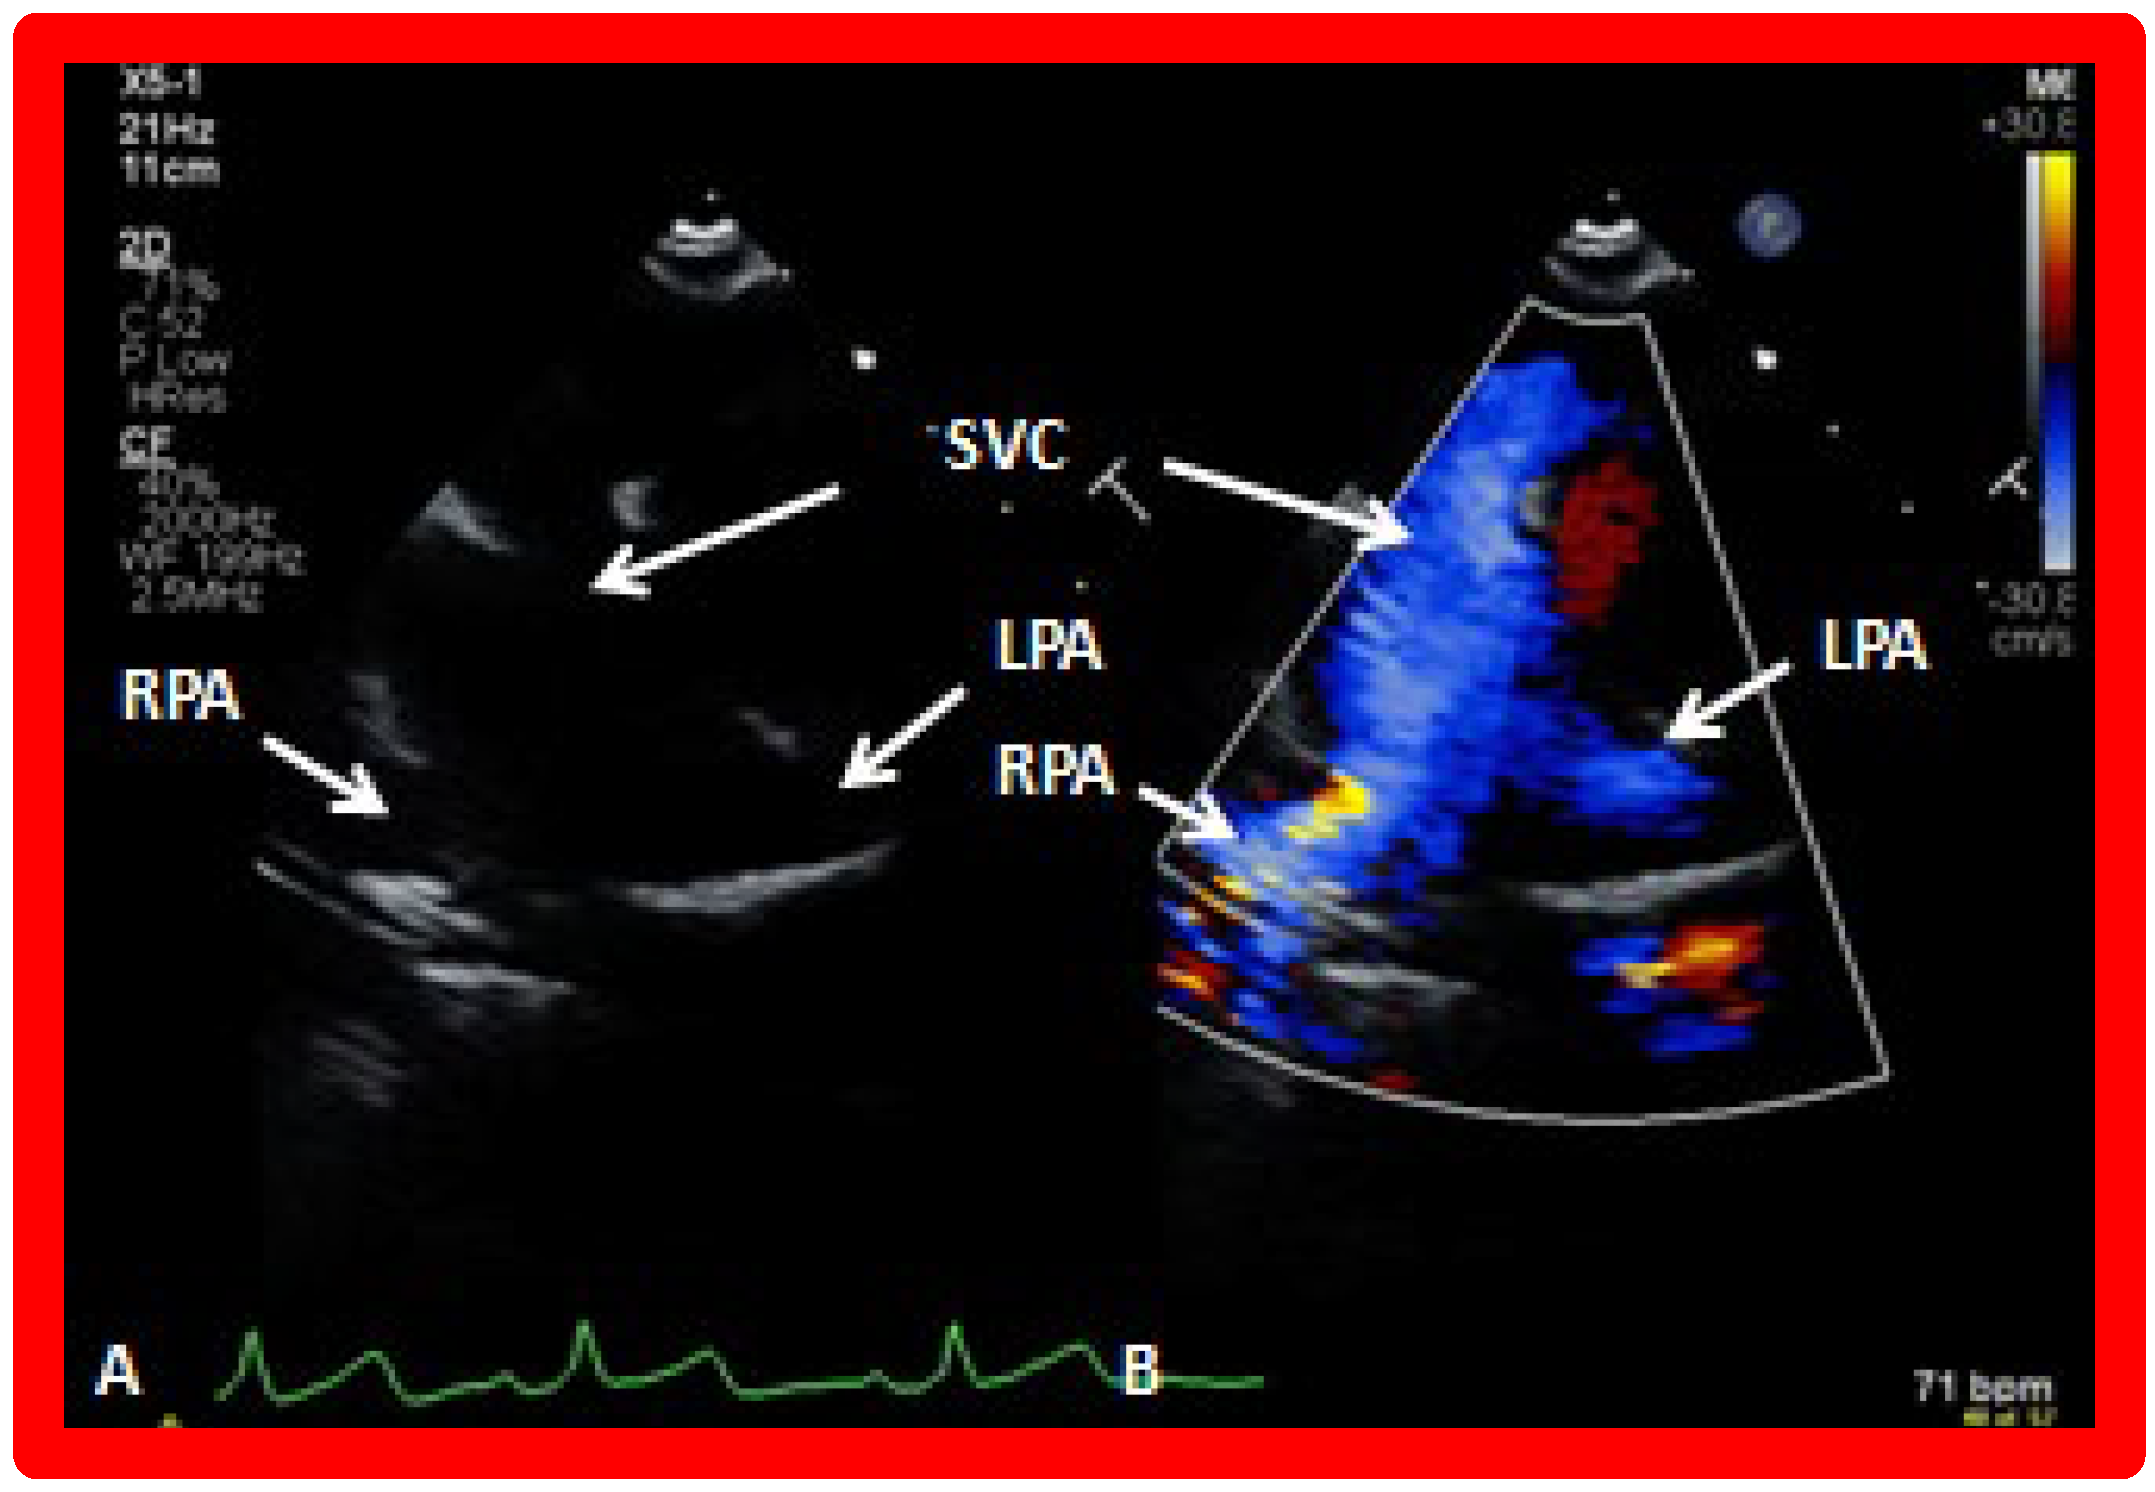

5.3. Echocardiographic Evaluation Following Bidirectional Glenn

Following bidirectional Glenn, the LV size is likely to decrease (normalize) and LV should maintain normal systolic function. This is because of decreased LV volume overload following bidirectional Glenn and the removal of aorto–pulmonary shunt. The 2D imaging of the bidirectional Glenn is difficult to accomplish, but color flow imaging (Figure 25A, Figure 26B, and Figure 27B) from a suprasternal notch or high parasternal views will help image the bidirectional Glenn. Low pulsed Doppler velocity across the superior vena cava (SVC)–PA junction (Figure 25B and Figure 26C) would indicate no obstruction. Turbulent and high velocity Doppler flow suggests the obstruction of the bidirectional Glenn shunt. The size of the branch PAs may be assessed with a combination of 2D and color flow imaging (Figure 26, Figure 27 and Figure 28).

Figure 25. Selected video frames from suprasternal notch view demonstrating bidirectional Glenn shunt; the superior vena cava (SVC) is shown emptying into the right (RPA) and left (LPA) pulmonary arteries by color flow imaging (A). Low Doppler flow velocity across the shunt (B) indicates unobstructed Glenn.

Figure 26. (A,B) Selected video frames from suprasternal notch view demonstrating bidirectional Glenn shunt. In (A), the right (RPA) and left (LPA) pulmonary arteries are shown by 2D. The superior vena cava (SVC) was not clearly seen. In (B), the SVC is shown emptying into the RPA by color Doppler (B). The LPA did not show color flow because it was in a different plane of imaging than RPA, but is seen by 2D (B). (C) Low Doppler flow velocity across the Glenn shunt indicates unobstructed flow.

Figure 27. Selected video frames from suprasternal notch view demonstrating bidirectional Glenn shunt; the superior vena cava (SVC) is shown emptying into the right (RPA) and left (LPA) pulmonary arteries by two dimensional (A) and color flow imaging (B). Both RPA and LPA are seen with color in contrast to that seen in Figure 26, probably related to both pulmonary arteries are in a similar echo plane.